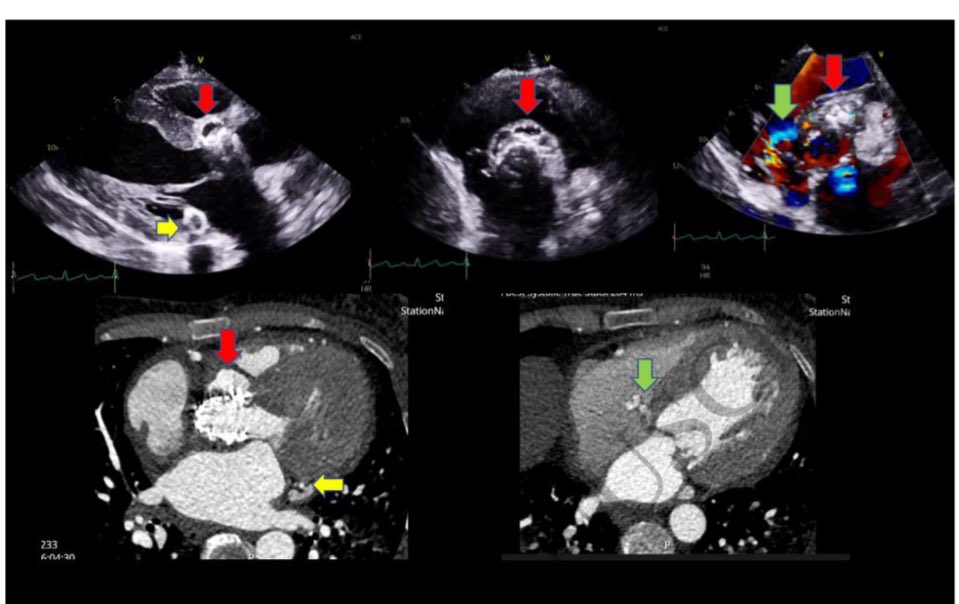

Honoured to have published this interesting case in #EHJIMP presenting a young patient with complex #TAVI endocarditis- key findings : large abscesses around #TAVI & posterior mitral annulus - fistula from LVOT ➡️ RA - severe MR Read here more on how we managed the patient ⬇️